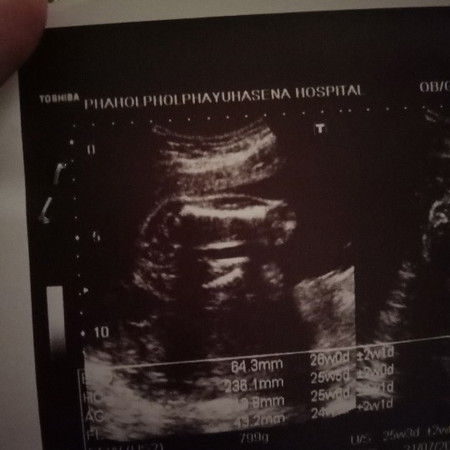

แบบนี้ชายหรือหญิงคะ

น่าจะชายหรือหญิงคะแบบนี้

ดูไม่ออกค่ะคุณแม่ ไม่เห็นปิกาจูและไม่เห็นกลีบค่ะ

ดูไม่ออกเลยค่ะ